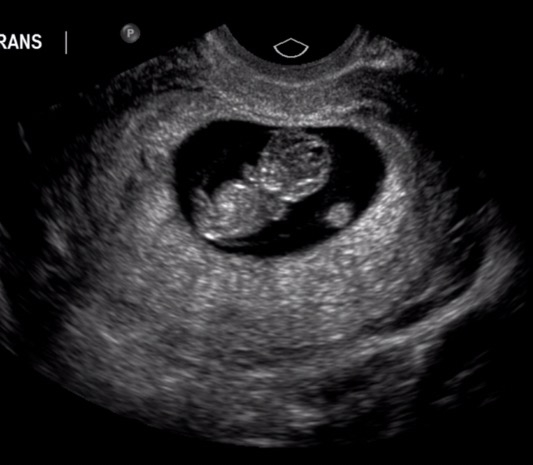

Finally! Met our rainbow baby yesterday, measuring spot on at 10w+1 and heartbeat at about 150/min. LO had the sweetest hiccups that we could see on the u/s, I'm in love!